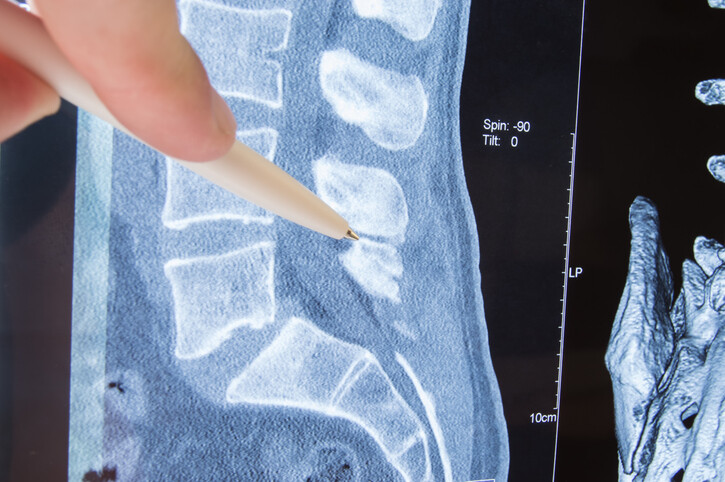

• ‘Enhanced Recovery’ protocol reduces opioid use in spinal surgery patients